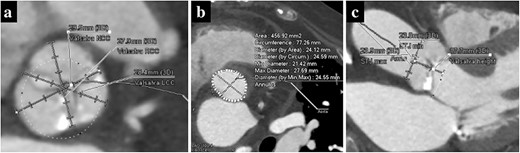

A 74-year-old woman with a history of interstitial pneumonia was admitted to the hospital with the chief complaint of dyspnea. The patient had been taking oral prednisolone (13 mg) for 9 years and home oxygen therapy for 6 years for interstitial pneumonia. Transthoracic echocardiography (TTE) showed an aortic valve area of 0.58 cm2, transvalvular peak velocity of 3.6 m/s, mean transvalvular pressure gradient of 28 mmHg and left ventricular ejection fraction of 33%. The patient was diagnosed with severe aortic stenosis. Computed tomography revealed a tricuspid aortic valve with an area of 456.9 mm2 and basal ring circumference of 77.3 mm, with a mildly calcified aortic annulus (Fig. 1a and b). We decided to perform transfemoral TAVR under local anesthesia. We chose the 26-mm SAPIEN 3 valve (Edwards Lifesciences, Irvine, CA, USA) for the following reasons: mild aortic annulus calcification, the possibility of future TAVR explants or transcatheter aortic valve in the transcatheter aortic valve (TAV-in-TAV) considering the patient’s age, and the fact that the self-expandable valves (SEVs) were unsuitable because of the small size of the sinus of Valsalva (Fig. 1c).

Preoperative computed tomography imaging showing a moderately calcified aortic annulus (a), an annulus area of 457 mm2 (b) and the short height of Valsalva (c).